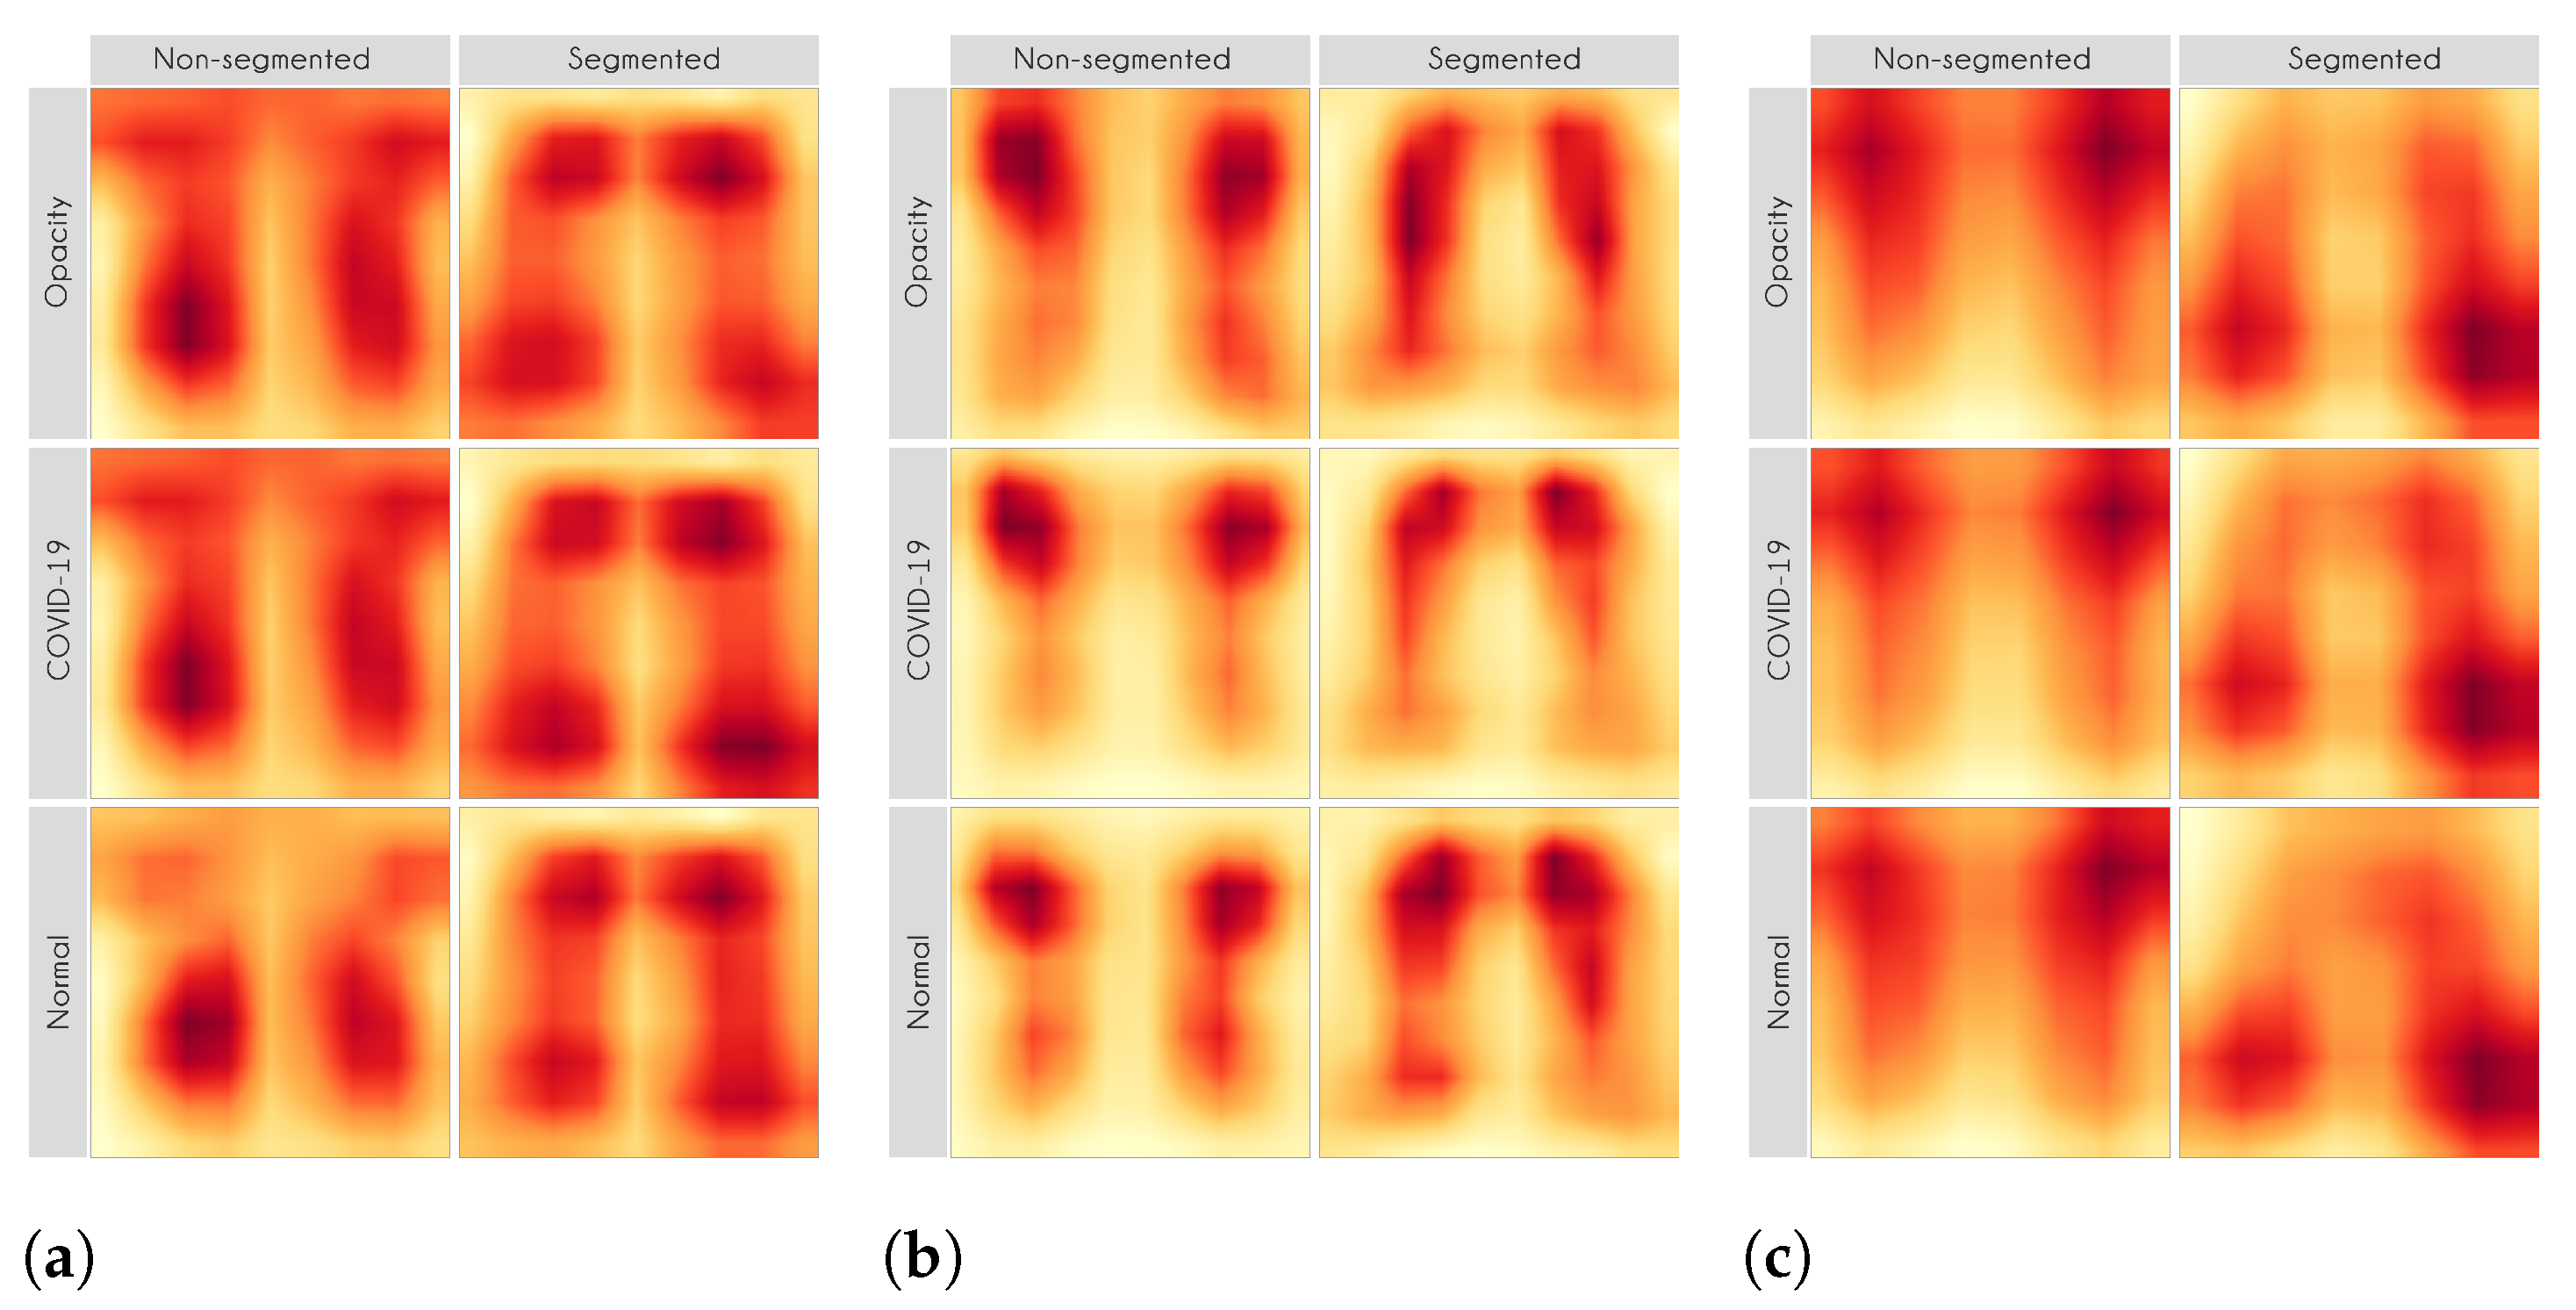

Figure 7 and

Figure 8 shows examples of important regions highlighted by LIME and Grad-CAM, respectively. In

Section 4, we will show that models trained using segmented lungs focus primarily on the lung area, while models trained using full CXR images frequently focus elsewhere.

Figure 13 presents some examples of the Grad-CAM explanation showing that the model is actively using burned-in annotations for the prediction. The LIME heatmaps presented in

Figure 10 show that exactly behavior for the classes Lung opacity and Normal in the non-segmented models, i.e., the model learned to identify the annotations and not lung opacities. The Grad-CAM heatmaps in

Figure 11 also show the focus on the annotations for all classes in the non-segmented models.

5.2. XAI

In this paper, we applied two XAI techniques: LIME and Grad-CAM. The reason for applying both is to evaluate the classification models thoroughly since they work differently. They have some significant differences and highlights: (i) LIME is model-agnostic, and Grad-CAM is model-specific; (ii) in LIME, the granularity of important regions is correlated to the granularity of the superpixel identification algorithm; (iii) Grad-CAM produces a very smoothed output because the dimension of the last convolution layer is much smaller than the dimension of the original input. Keep in mind that such techniques are not definitive. They can complement and corroborate with each other. Thus, we can increase the model reliability in a real-world context by using a more comprehensive approach.

Figure 10 and

Figure 11 demonstrate that the models using full CXR images are misleading because they focus a lot on the left and right uppermost regions, which is usually the location of burned-in annotations.